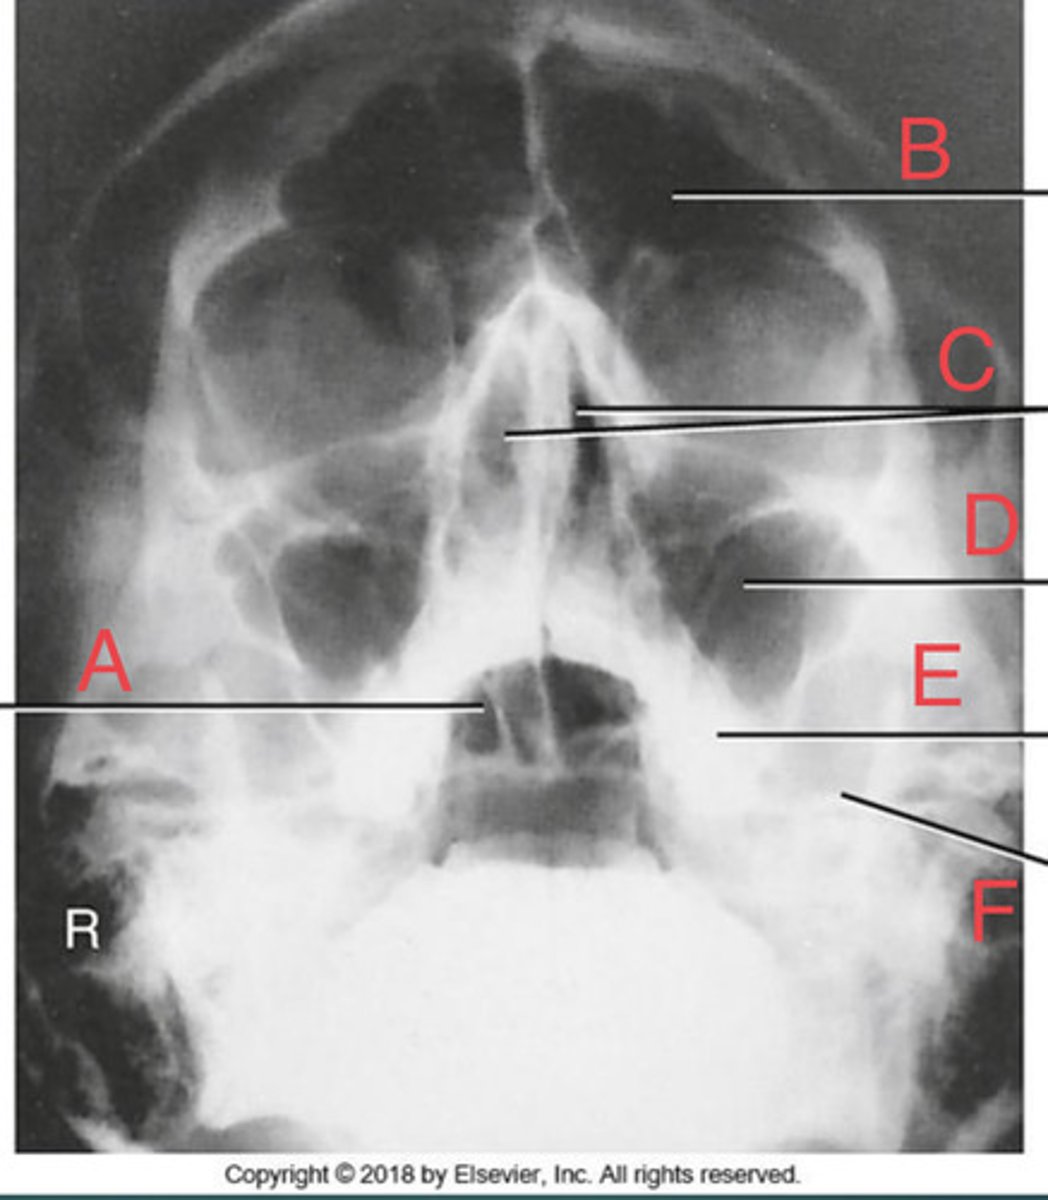

Waters sinus method

What projection?

r. frontal sinus of the frontal bone

A.

R. Maxillary sinus of maxilla

B.

R. petrous ridge of temporal bone

C.

bony nasal septum

D.

L. inferior orbital fissure of sphenoid bone

E.

Sphenoid sinus of sphenoid bone

F.

bony nasal septum

E.